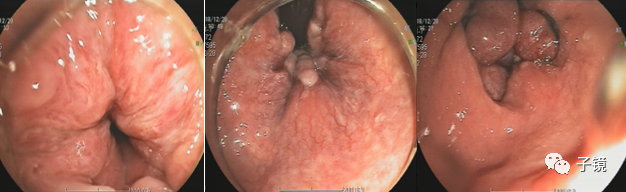

内痔脱垂

外痔